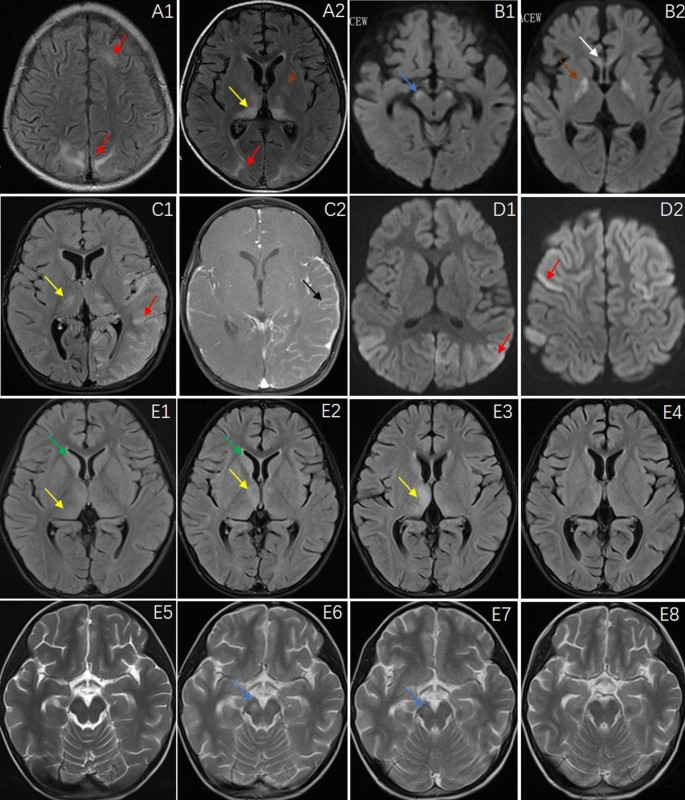

Brain MRI (Fig. 2) revealed abnormalities in 10 patients (66.7%). The most common sites of lesions were the cerebral cortex (widely distributed across the frontal, parietal, occipital and temporal lobes), thalamus, caudate nucleus, cerebral peduncle, white matter, hippocampus, globus pallidus and corpus callosum. Electroencephalography (EEG) recordings revealed a slow wave background in 13 patients (86.7%), 2 (21.43%) of whom had bursts of delta rhythm (Fig. 3). Epileptiform discharges, originating from the frontal and temporal lobes, were found in 4 patients (26.7%), and one patient manifested with epilepsia partialis continua (EPC). All 15 patients underwent lumbar puncture examinations, 5 showed elevated WBC in CSF, and 4 showed elevated protein in CSF. Changes in the CSF were not very common in CASPR2-related patients. The CSF pathogen tests were negative in all patients.

Brain MRI features of patients N.3, N.5, N.6, N.8 and N.10. Patient N.3, a 6-year-old boy, had a clinical-radiological presentation of Morvan syndrome including multifocal lesions in the occipital and parietal cortex and thalamus (A1, A2). Patient N.5, a 5-month-old boy, presented with encephalopathy and bilateral MRI abnormalities in the globus pallidus, corpus callosum and cerebral peduncle (B1, B2). Patient N.6, a 2-year-old girl, had a clinical-radiological presentation of autoimmune encephalitis, including cortical lesions in the frontal, parietal, occipital and temporal lobes and thalamus and cortical lesions showing enhancement with gadolinium administration (C1, C2). Patient N.8, a 5-year-old girl, presented with two episodes of fever and seizures within a week. Brain MRI showed extensive cortical lesions in the frontal, parietal, occipital and temporal lobes (D1, D2). Patient N.10, a 6-year-old boy, presented with fever, ataxia, slow responses. Brain MRI (E1–E8) showed a series of changes including lesions in the thalamus, caudate nucleus and cerebral peduncle (E1/E5, E2/E6, E3/E7, E4/E8, representing D4, D16, D30, and D50 after onset, respectively). Fluid-attenuated inversion recovery sequences were used in (A1, A2, C1, E1–E4, and C2, which show enhancement with gadolinium administration. T2 sequences were used in (E5–E8). Diffusion weighted imaging was used in (B1, B2, D1 and D2). Red arrows represent multiple cortical lesions, yellow arrows: thalamus, blue arrows: cerebral peduncle, green arrows: caudate nucleus, brown arrows: globus pallidus, white arrow: corpus callosum, black arrow: meningeal enhancement.

Patient N.3, a boy aged 6 years, developed neuromyotonia and neuropathic pain, movement disorders, sleep disorders, irritability, eating difficulties and cognitive changes. Both CASPR2 and GABABR antibodies were detected in his serum and CSF. He was treated with intravenous immune globulin (IVIG) (2 g/kg/day for 5 days) and IV methylprednisolone (IVMP) (3 cycles of 20 mg/kg/day for 3 days alternating with 4 days of rest). One month later, his symptoms had not been relieved, his CASPR2 titers had not decreased, and brain MRI (Fig. 2-A1/A2) revealed new lesions. He was treated with rituximab (375 mg/m2, once a week, 4 times) and improved remarkably. One month after rituximab treatment, all his symptoms were relieved, his MRI results had become normal, and the CASPR2 antibody test was negative. Moreover, during the treatment, we found that carbamazepine had a significant effect on relieving the symptoms of myotonia.

Patient N.5 was the youngest patient, only 5 months old at symptom onset. His main symptoms included fever, recurrent seizures, disturbance of consciousness, and irritability. Brain MRI (Fig. 2-B1/B2) showed lesions in the globus pallidus, corpus callosum and cerebral peduncle. The WBC, protein, bacterial culture and macrogene examination for virus nucleic acid in CSF were normal. CASPR2 antibody positive was found in the serum. He received symptomatic treatment, including assisted ventilation. His symptoms gradually improved, and his development gradually progressed after rehabilitation training. At the age of 2 years and 6 months, he could speak and walk independently.

Patient N.6, a girl aged 2 years, developed fever, recurrent seizures, unconsciousness, sleep and movement disorders, and psychological symptoms. Both CASPR2 and NMDAR antibodies were detected. Brain MRI (Fig. 2-C1/C2) showed extensive lesions in the cortex and thalamus, with meningeal enhancement of the cortical lesions. The symptoms in the acute stage were very severe but improved greatly after IVIG and half a year of steroid treatment. The patient was able to attend school normally and had normal intelligence.

Patient N.8, a girl aged 5 years, presented with two episodes of fever and seizures within a week. The symptoms were resolved without treatment. Brain MRI showed extensive cortical lesions (Fig. 2-D1/D2). However, we still used IVIG to prevent aggravation of the clinical symptoms. During the 15-month follow-up, no symptom recurrence was observed.

Patient N.10, a boy aged 6 years, was admitted to the hospital because of fever, ataxia, and slow responses. EEG showed a low wave background, and brain MRI showed lesions in the thalamus and caudate nucleus (Fig. 2-E1/E5), with elevated WBCs in the CSF. Anti-CASPR2 antibody was positive in the CSF and negative in the serum, while NMDAR was initially negative in both the CSF and serum. He was treated with IVIG+IVMP, and the clinical symptoms were improved. One month after he was discharged from the hospital, he presented with hemiplegia and irritability. Brain MRI revealed new lesions in the cerebral peduncle (Fig. 2-E2/E6), and anti-NMDAR antibody was positive in the CSF, but anti-CASPR2 antibody was negative. He was treated with IVMP again and then rituximab. The lesions on brain MRI (Fig. 2; E3/E4/E7/E8, E1/E5, E2/E6, E3/E7, and E4/E8 represent D4, D16, D30, and D50 after onset, respectively) were decreased after immunotherapy. The hemiplegia improved (at 1 month after discharge) but incompletely, and the patient remains in follow-up.